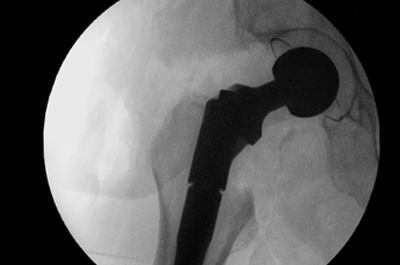

Höchste Qualitätsstandards für hüftgelenknahe Femurfrakturen im SGK bestätigt

Das Sankt Gertrauden Krankenhaus in Berlin hat die strengen Qualitätsanforderungen des G-BA für die Behandlung von Patient:innen mit hüftgelenknahen Femurfrakturen erfüllt, bestätigt durch eine Prüfung der MD Berlin-Brandenburg.